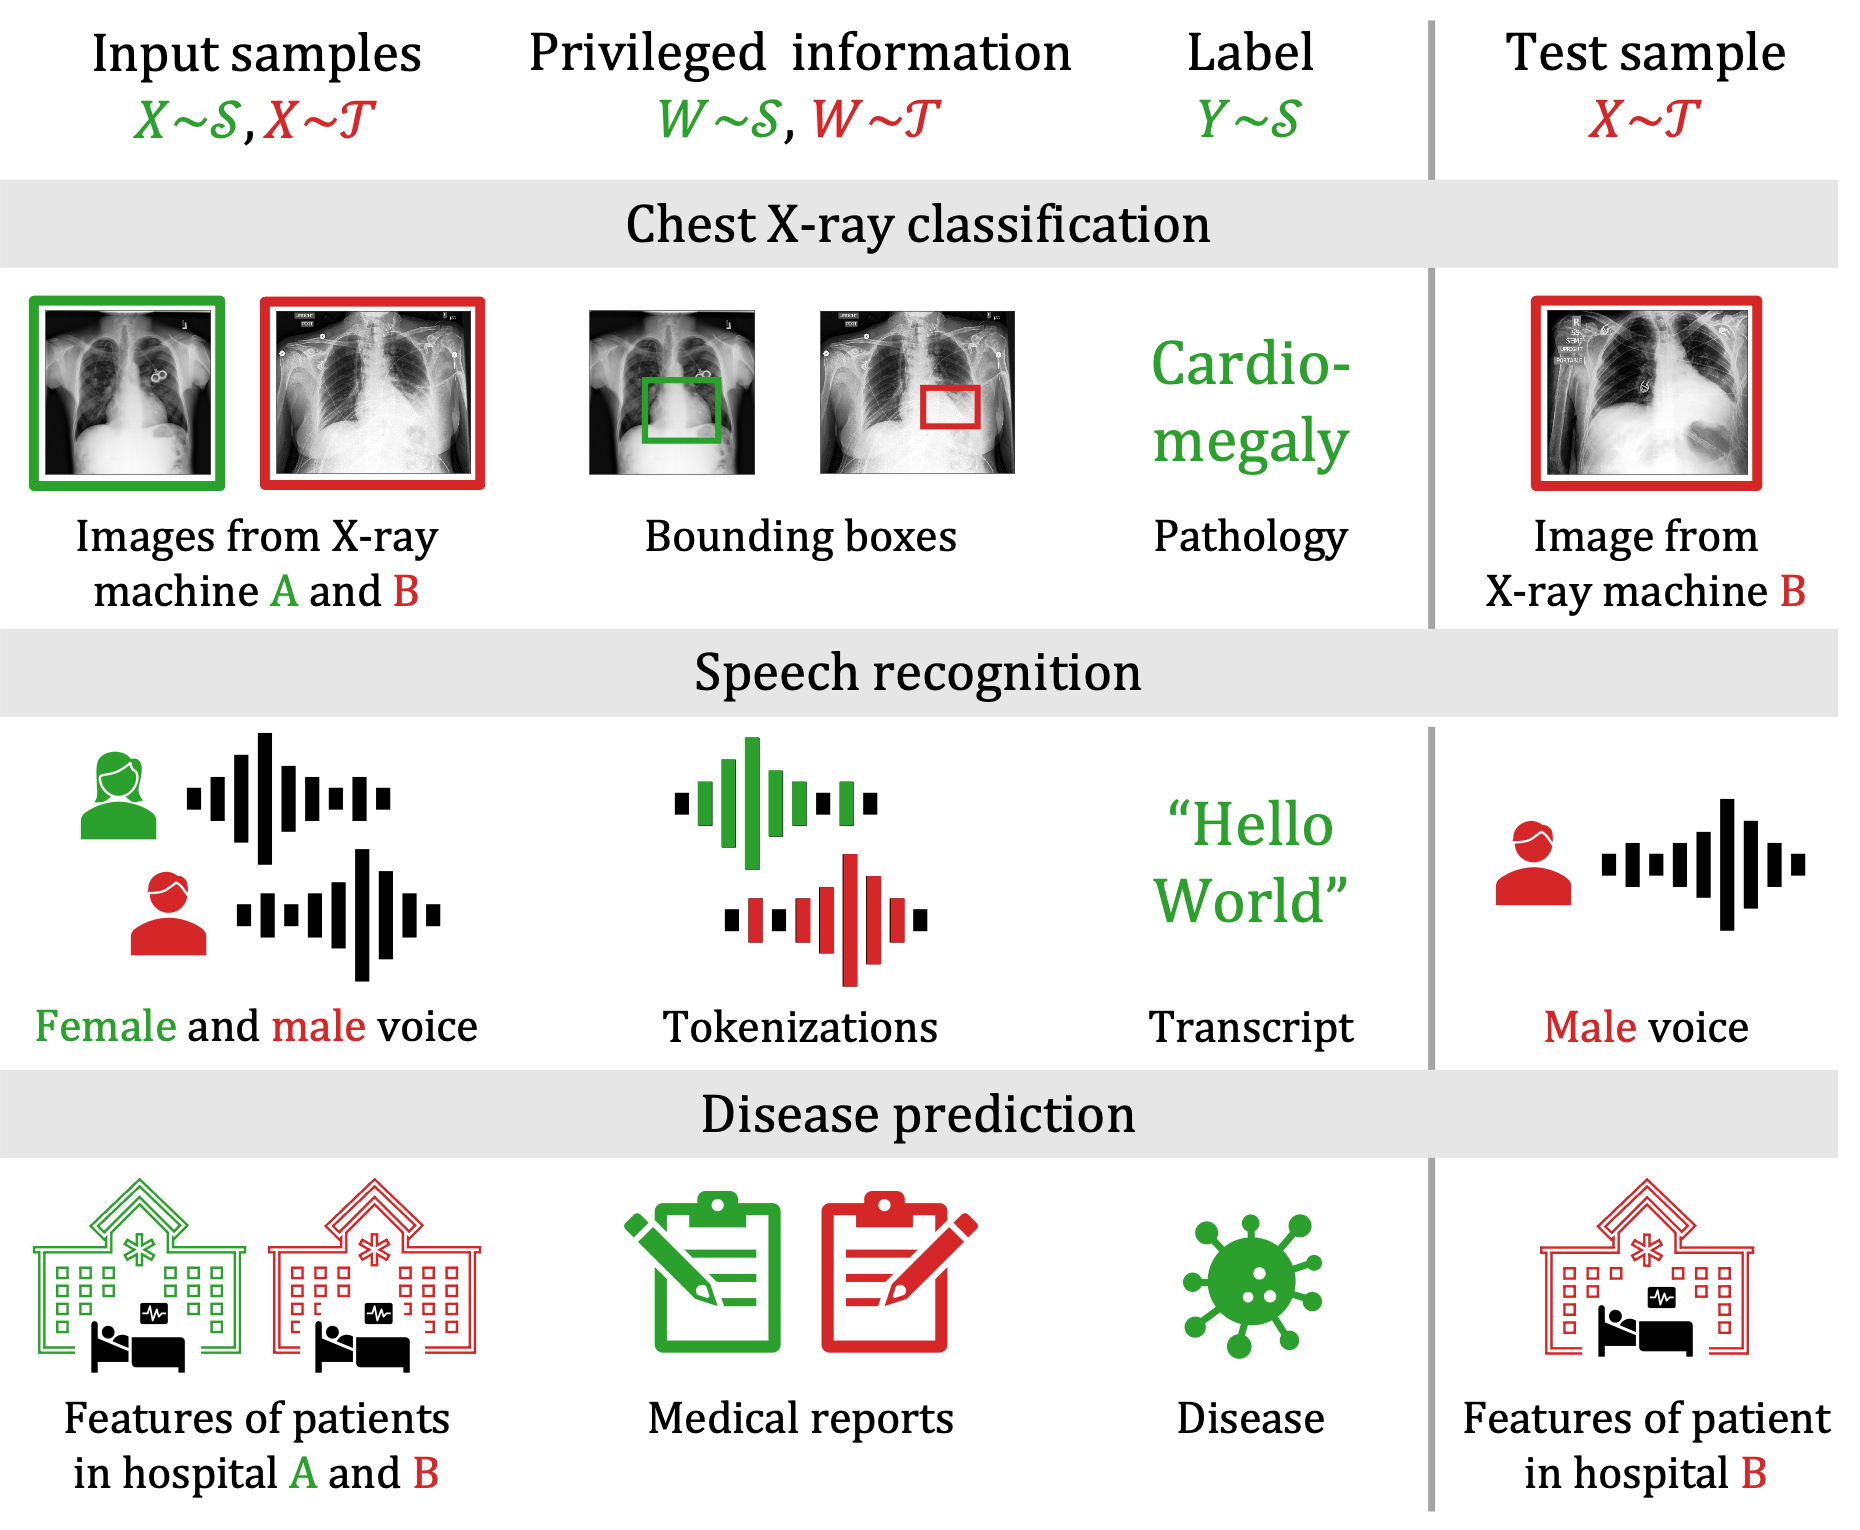

Incorporating side information in training has been proposed as a means to improve generalization without domain shift. Through learning using privileged information (LUPI) (Vapnik & Vashist, 2009; Lopez-Paz et al., 2016), algorithms that are given access to auxiliary variables during training, but not in deployment, have been proven to learn from fewer labeled examples compared to algorithms learning without these variables (Karlsson et al., 2021). In X-ray classification, privileged information (PI) can come from graphical annotations or clinical notes made by radiologists, which are unavailable when the system is used (see Figure 1). While PI has been used also in domain adaptation, see e.g., (Sarafianos et al., 2017; Vu et al., 2019), the literature has yet to characterize its benefits in generalizing across domains.

We define domain adaptation by learning using privileged information (DALUPI) as follows. During training, learners observe samples of covariates , labels and privileged information from in a dataset , as well as samples of covariates and privileged information from , . At test time, the trained models only observe covariates from . Our goal remains to minimize the target risk (1). Figure 1 illustrates several applications with this structure.